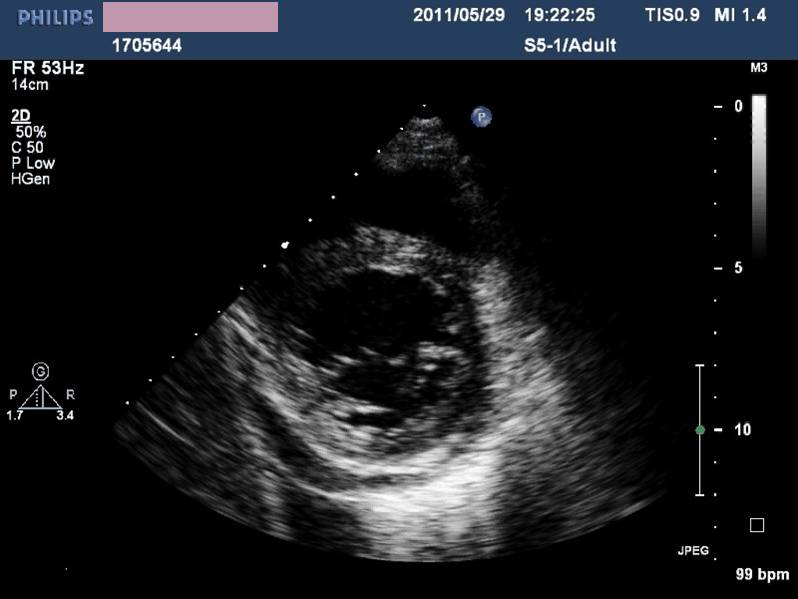

——床旁超声心动:节段性室壁运动异常,左房增大,轻度二尖瓣关闭不全,左室收缩功能减低,LVEF 45%,少量心包积液

现病史-超声心动

急性左心收缩功能不全